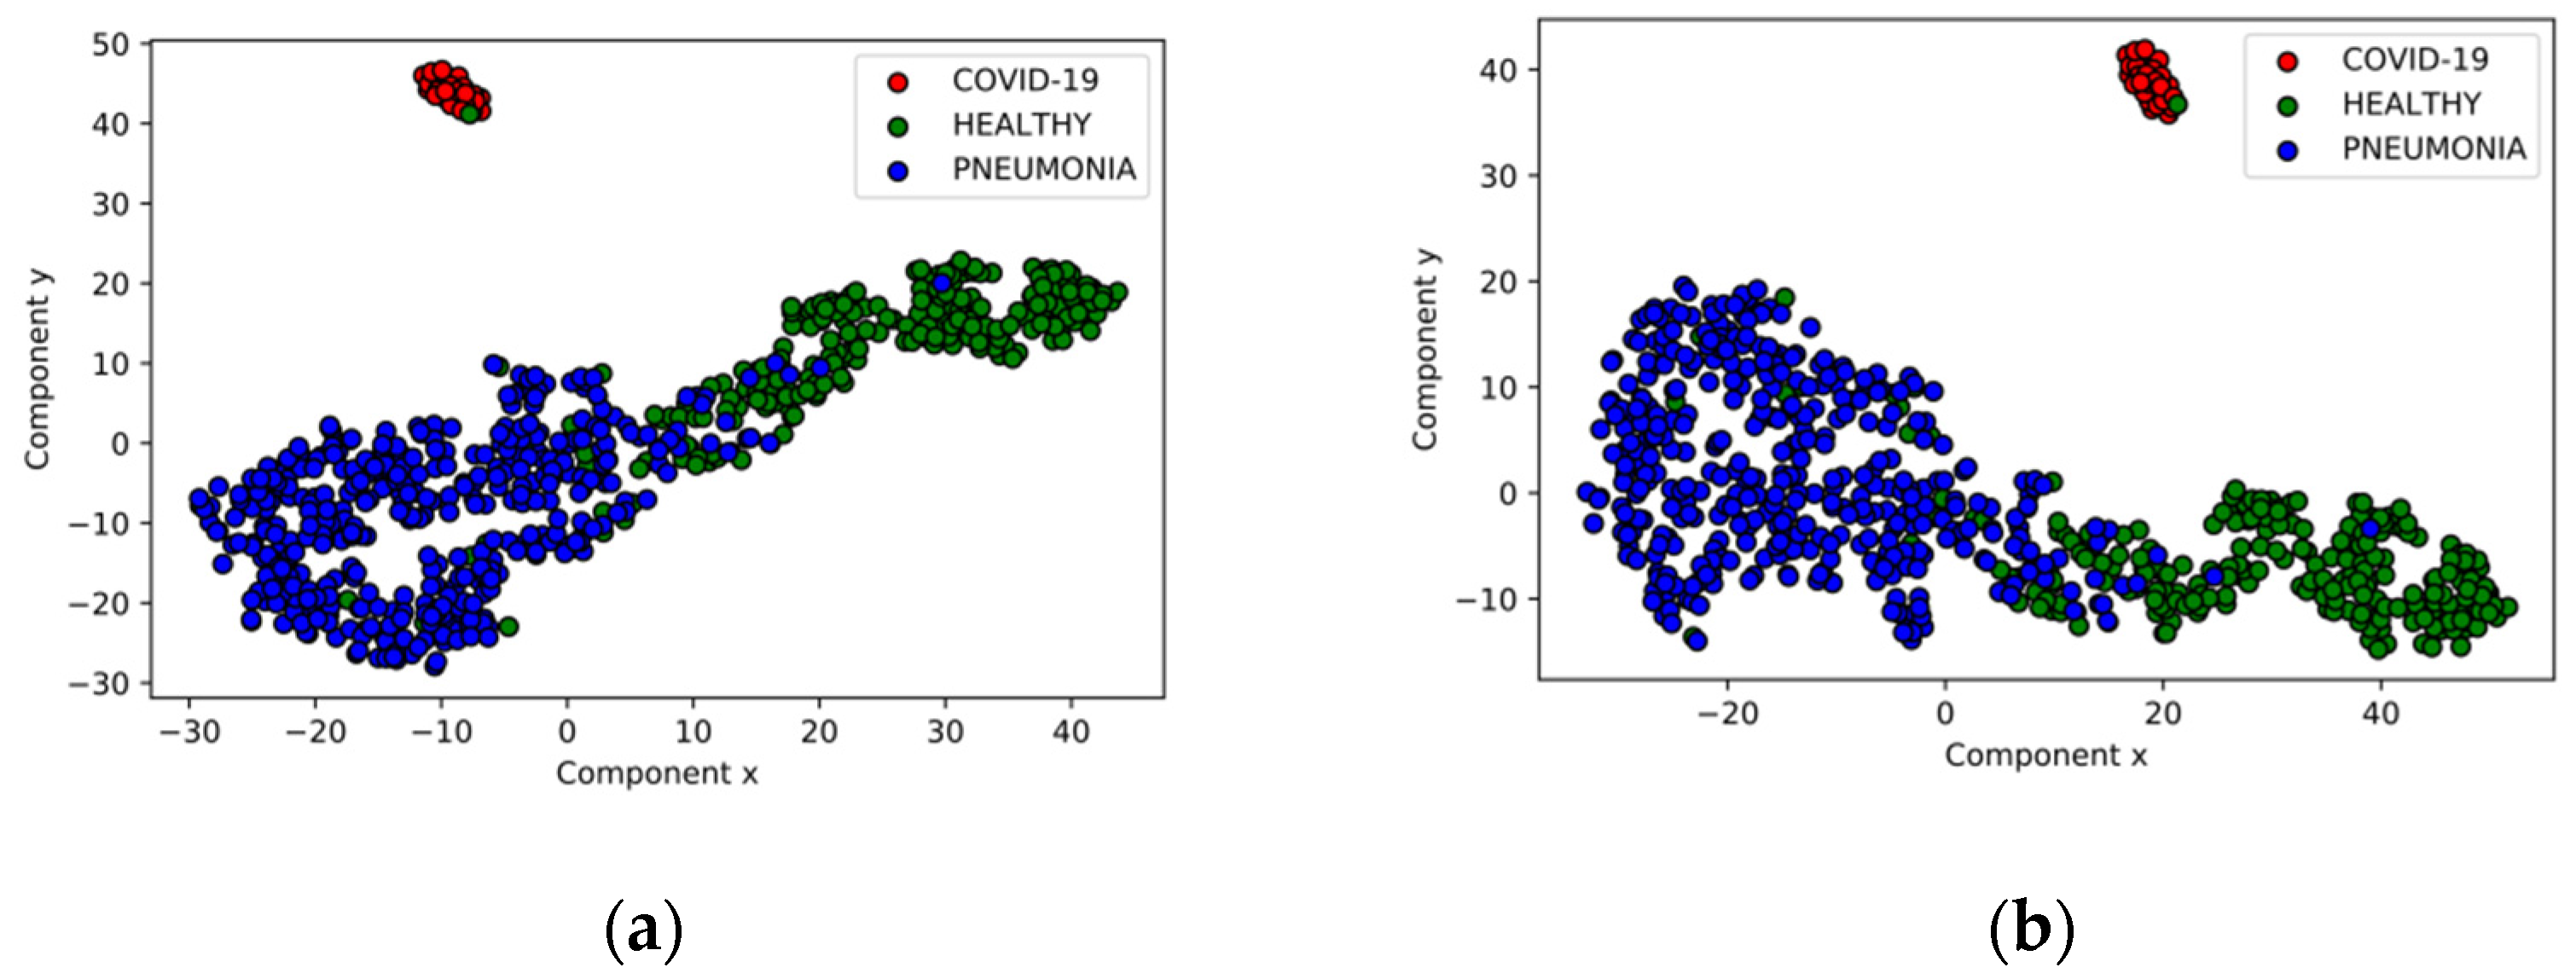

5.2. Validation Set Results

5.4. Disease Screening